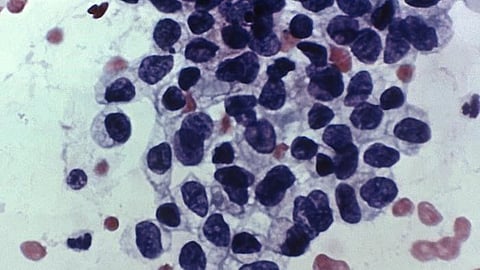

To conduct this study, Ogino and lead author Tomotaka Ugai, MD, PhD, also of the Department of Pathology, and their colleagues first analyzed global data describing the incidence of 14 different cancer types that showed increased incidence in adults before age 50 from 2000 to 2012. Then, the team searched for available studies that examined trends of possible risk factors including early life exposures in the general populations. Finally, the team examined the literature describing clinical and biological tumor characteristics of early-onset cancers compared to later-onset cancers diagnosed after age 50.